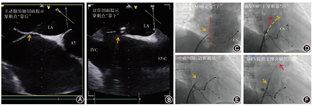

连续性纳入上海市第十人民医院自2014年4月至2019年3月31日拟行LAAC的房颤患者。共计563例经过筛选尝试行左心耳封堵术(图8),550例植入左心耳封堵器,13例没有植入封堵器,未植入的原因包括1例双侧股静脉变异致鞘管不能通过放弃手术;2例左心耳造影前发现"心包填塞"放弃继续LAAC;4例尝试植入PLO失败且拒绝择期行补救性DLO,均为开口大的左心耳,2例合并可用深度较浅(图9 A~D);5例完成左心耳造影后放弃尝试植入PLO,其中3例为多分叶且较浅(图9 E~G),1例为极小左心耳(图9H),1例为反鸡翅且可用深度较浅(图9I);1例左心耳开口较大且口部梳状肌放弃植入封堵器。该例尝试植入36 mm×40 mm LAmbre,释放封堵器后脱落至左心房内,成功经导管回收(图9 J~K),放弃继续植入封堵器。

3例在完成LAA造影后,放弃尝试植入PLO,择期行LAmbre封堵器补救,2例成功(1例使用最大型号LAmbre封堵器36 mm×40 mm ,1例使用特殊型号LAmbre封堵器18 mm×32 mm,图10),1例使用2个LAmbre封堵器但仍封堵失败(图11)。

6例尝试植入PLO不成功,行补救性DLO植入,均成功封堵,使用LAmbre封堵器5例和Leftear封堵器1例。其中3例使用较大型号封堵器(图12),31 mm×35 mm 1枚(Leftear封堵器)和36 mm×40 mm 2枚,1例使用最小型号LAmbre封堵器(图13)16 mm×22 mm、2例使用特殊型号LAmbre封堵器24 mm×36 mm及22 mm×34 mm。

19例左心耳形态不合适PLO植入的病例中,有10例左心耳不适合使用DLO植入失败或未尝试也拒绝择期植入DLO,有9例使用DLO补救。从左心耳形态分析,1例为开口极小且分叶(图13) A,开口大(>32 mm)5例(图10A、图11、图12A、图12B、图12C)、分叶且较浅3例(图10B、图13B、图13C)。从补救使用的DLO分析,使用大尺寸封堵盘(封堵盘>32 mm)的封堵器达到88.9% (8/9),1例使用最小型(固定盘16 mm,封堵盘22 mm),提示DLO比PLO覆盖更多的左心耳开口尺寸。使用"小伞大盘"特殊型号封堵器3例,封堵盘比固定盘大12~14 mm,均植入于多分叶的病例(图10B、图13B、C),固定盘固定于某一分叶。提示DLO中"小伞大盘"的特殊类型,更能适用于多分叶的左心耳。